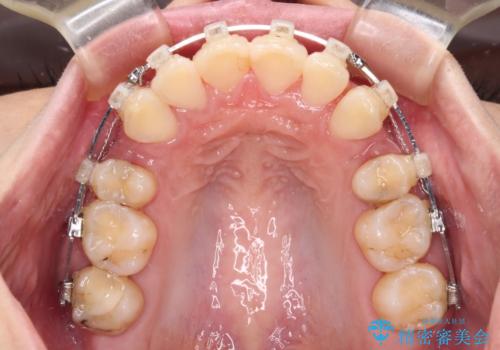

- クリアブラケット

舌の突出癖が顕著で、上顎歯列は完全なV字型となっている状態でした。

下顎歯列にも八重歯があり、上下左右の第一小臼歯4本を抜歯して、ワイヤー装置にて矯正治療を行うこととしました。

どこまで口元の突出感を改善できるのか不安でしたが、舌のトレーニングをしっかりと行ってくださり、我々も驚くほど劇的に改善することができました。